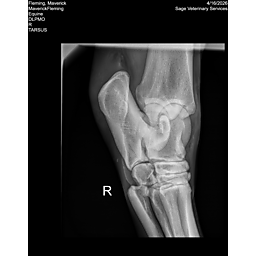

**Maverick sells at the Colorado Horse Sale’s Best of the West Select Sale on May 30th in Castle Rock, CO - He will complete the riding & handling Sift Exam, baseline veterinary exam, and will sell with 4 total radiographs (DLPMO & Front Foot Lateral)**